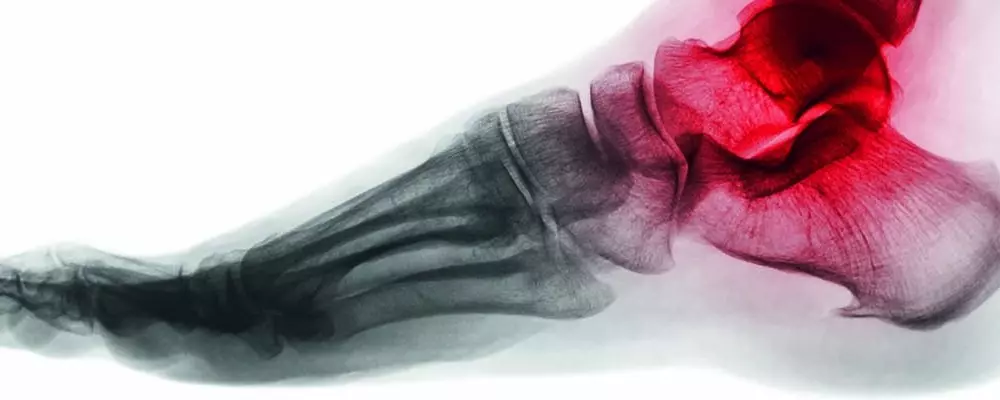

Temat sto piątego wydania czasopisma Praktyczna Fizjoterapia i Rehabilitacja brzmi "Metody oceny oraz uśmierzania bólu stosowane w fizjoterapii". Ból towarzyszy niemal każdej chorobie bądź patologii i jest sygnałem świadczącym o nieprawidłowościach w organizmie człowieka. Zachęcamy do zapoznania się z metodami zmniejszania bólu.

- patologie trzeszczek,